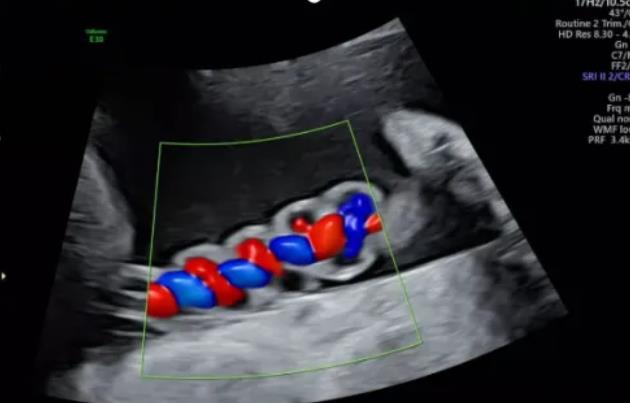

聲像圖特征:臍動(dòng)脈表現(xiàn)為過度螺旋,臍血管變細(xì),縱切面呈“麻花狀”,橫切面呈“鼠眼狀”;

2、臍帶螺旋過松

聲像圖特征:胎兒臍帶縱切面示血管呈平行排列,螺旋稀少,彩色多普勒血流成像示臍帶血管內(nèi)充滿的紅藍(lán)血流呈平行排列,麻花狀螺旋消失。